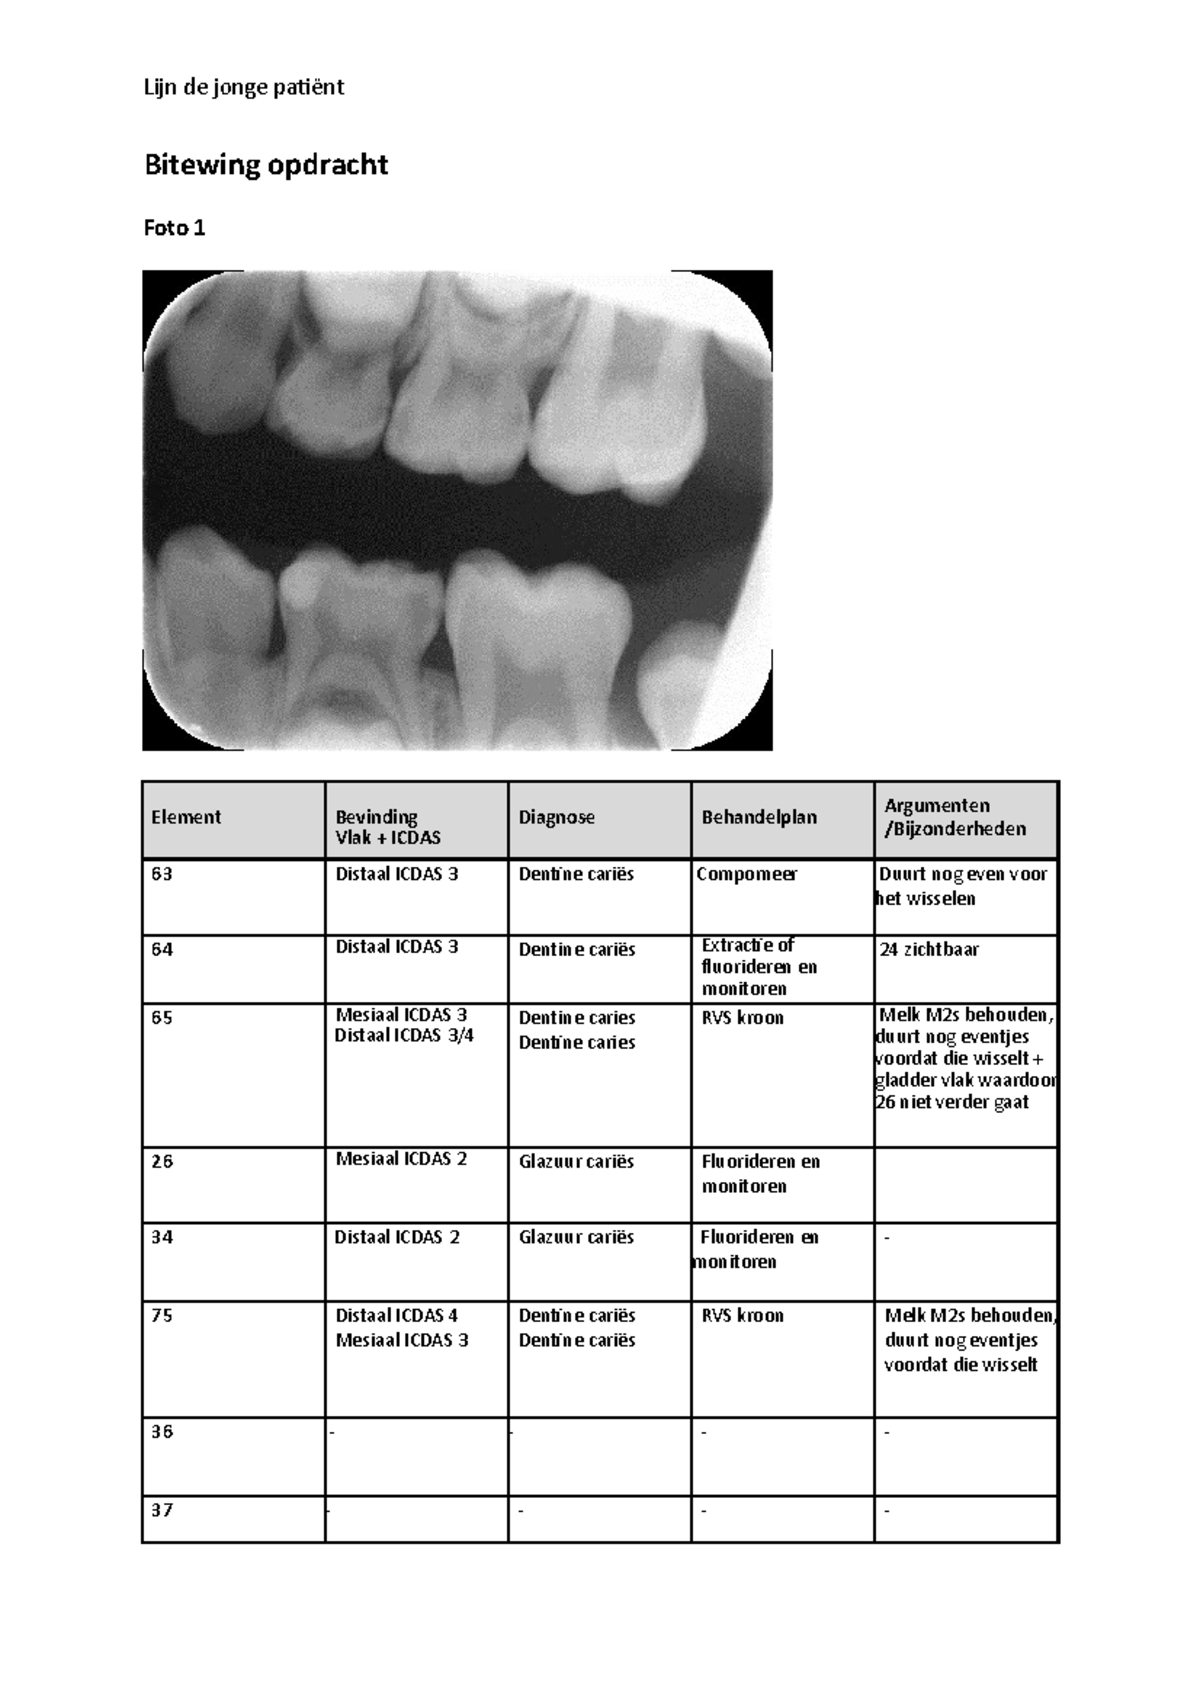

From www.studeersnel.nl

Bitewing opdracht Bitewing opdracht Foto 1 Element Bevinding Vlak Bitewings Four Films Cpt Code The service code does not discriminate between either process. Crosswalk of cpt codes to cdt codes. What is d0274 dental code? Bitewings Four Films Cpt Code.